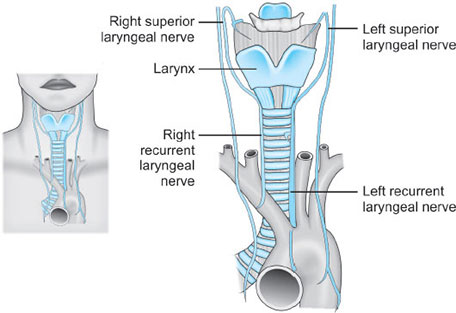

NERVES (FIG. 11)

The main nerves of the larynx are the recurrent laryngeal nerves and the internal and external branches of the superior laryngeal nerves (from 11vagus nerve). The external branch of the superior laryngeal nerve supplies motor innervation to the cricothyroid muscle. All other motor supply to the laryngeal musculature is provided by the recurrent laryngeal nerve.

The recurrent laryngeal nerve also provides sensory innervation to the larynx below the vocal cords.

There is an intimate and important relationship between the nerves that supply the larynx and the vessels that supply the thyroid gland.

The external branch of the superior laryngeal nerve descends over the inferior constrictor muscle of the pharynx immediately deep to the superior thyroid artery and vein as these pass to the superior pole of the gland; at this site the nerve may be damaged in securing these vessels (Figs. 12A and B).

The recurrent laryngeal nerve, as it ascends in the tracheoesophageal groove, is overlapped by the lateral lobe of the thyroid gland, and here comes into close relationship with the inferior thyroid artery as this passes medially, behind the common carotid artery, to the gland. The artery may cross posteriorly or anteriorly to the nerve, or the nerve may pass between the terminal branches of the artery. On the right side, there is an equal chance of locating the nerve in each of these three situations; on the left, the nerve is more likely to lie posterior to the artery.